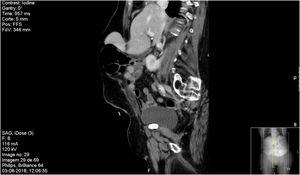

Manejo quirúrgico del carcinoma suprarrenal con trombo tumoral en la vena cava inferior

Beatriz Villota, Mikel Prieto, Arkaitz Perfecto, Andrés Valdivieso

Cir Esp. 2024;102:175